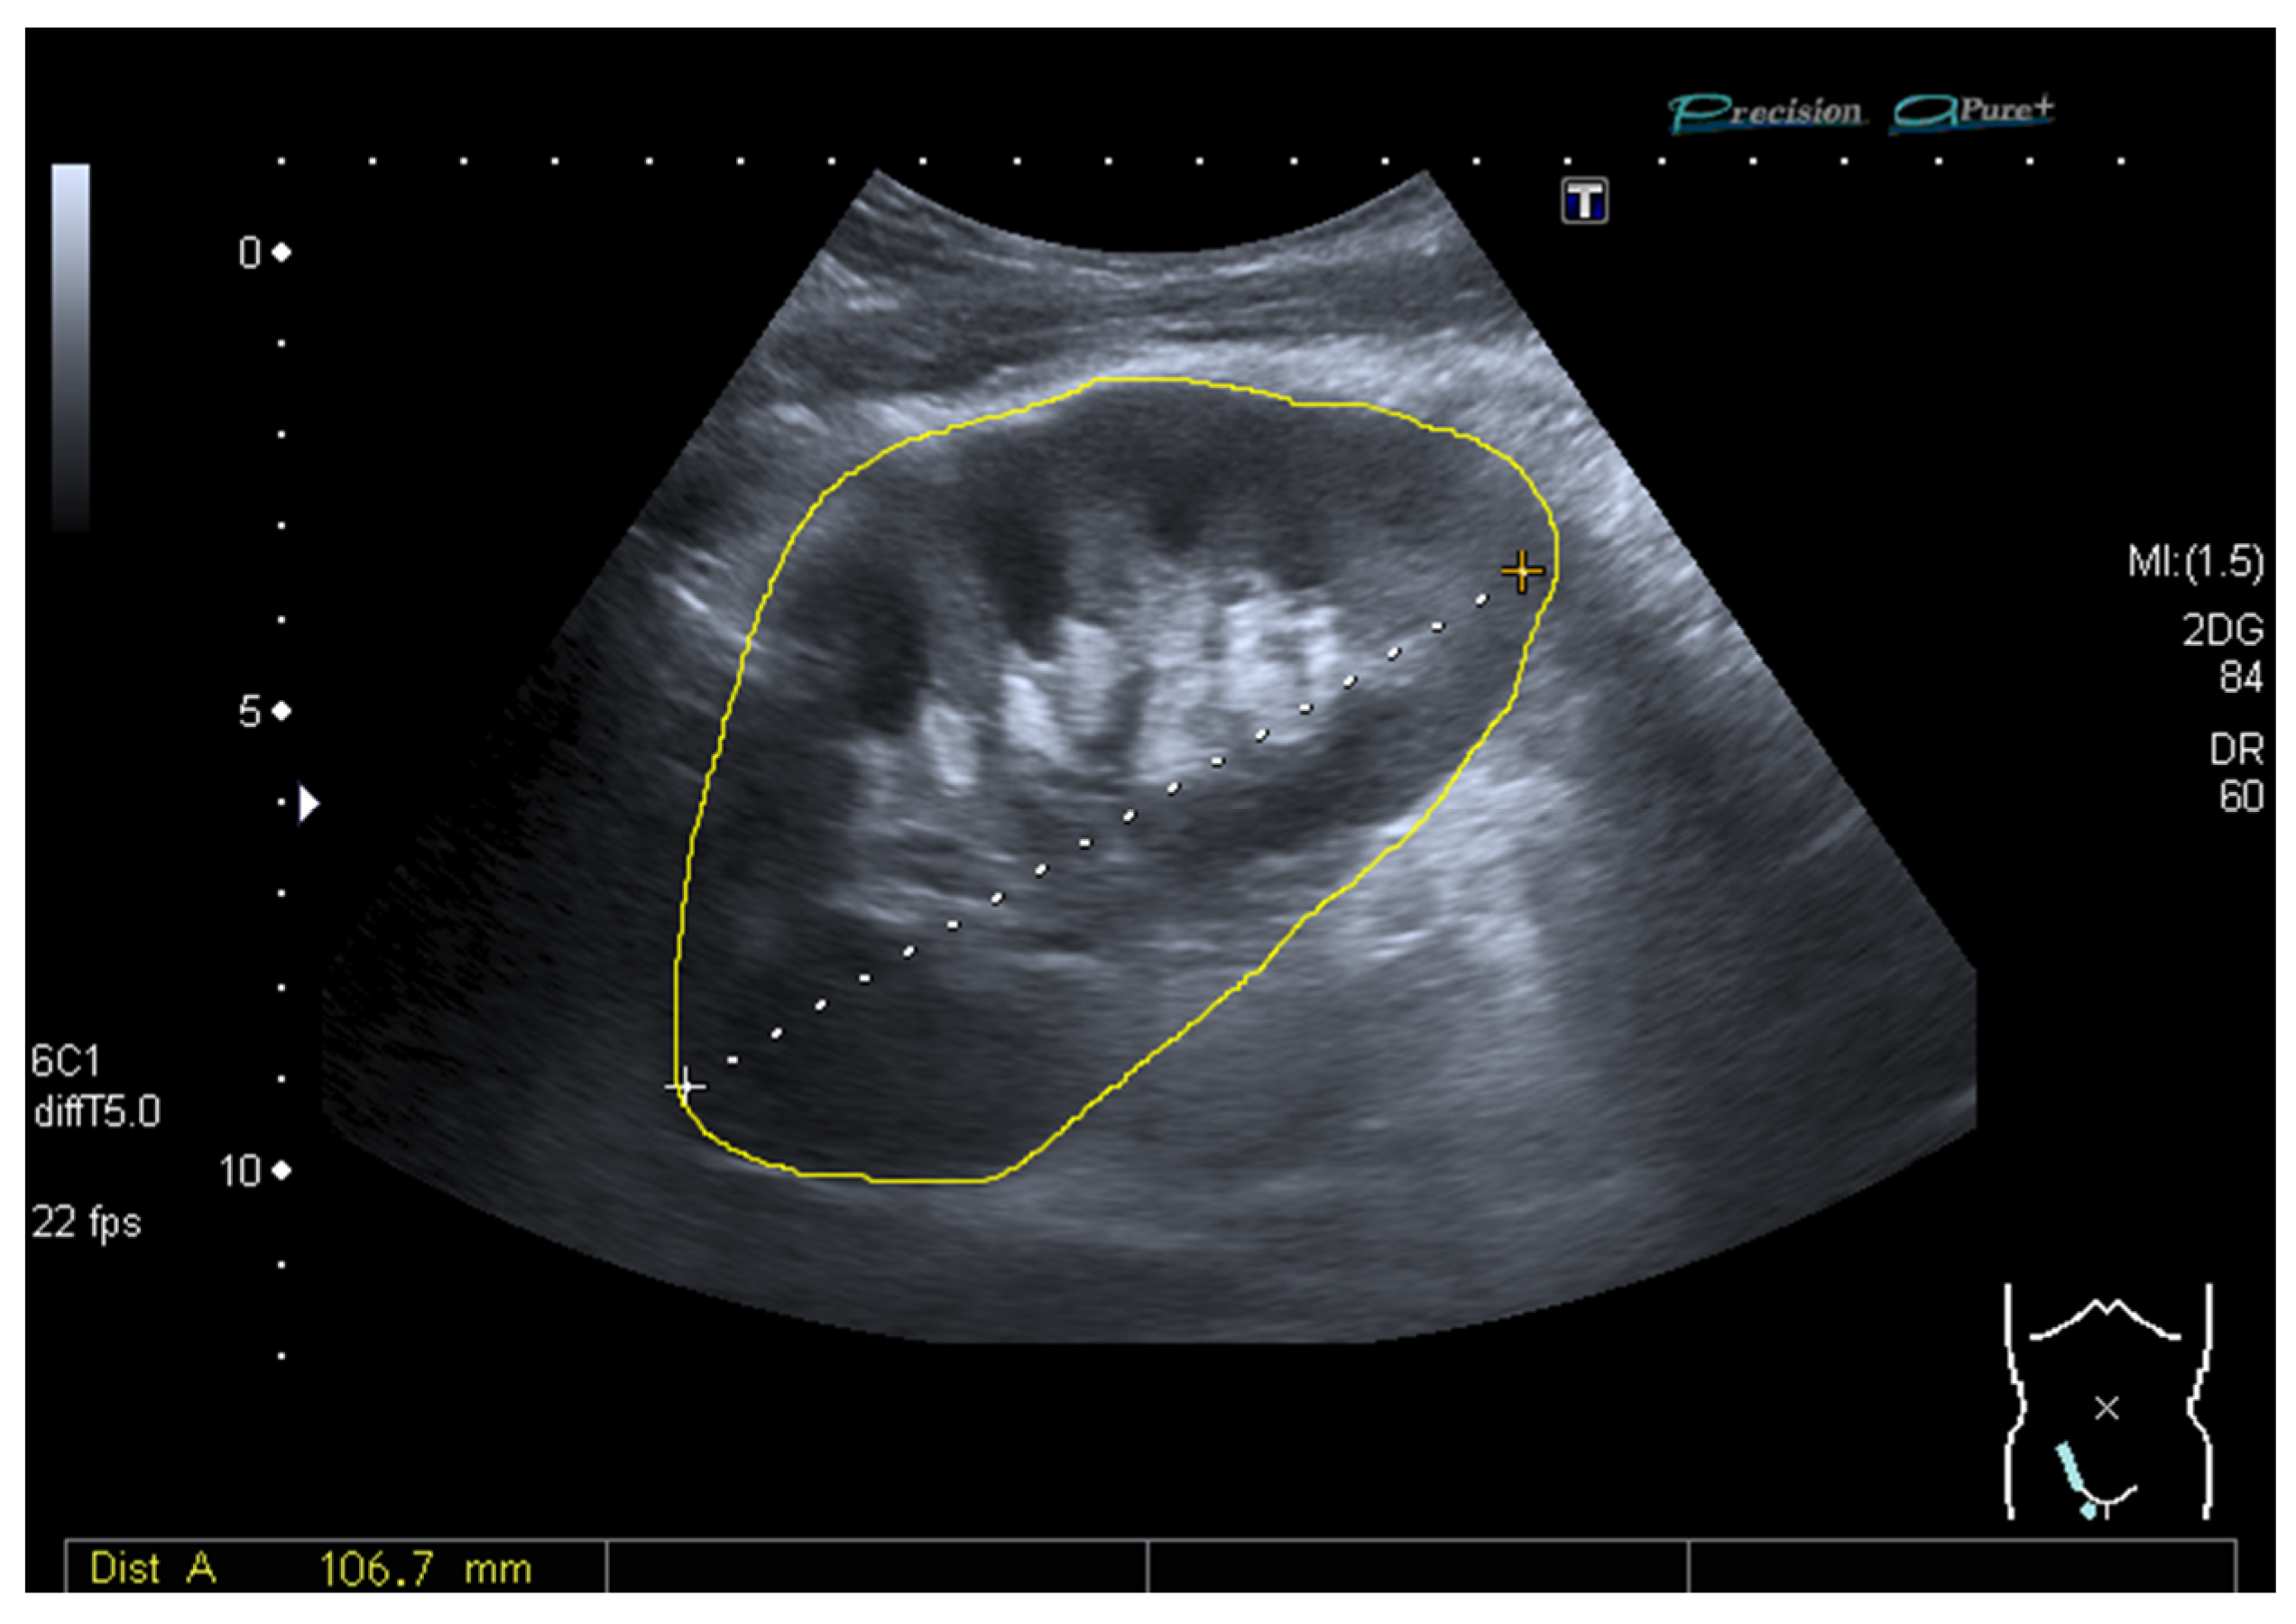

2.3. Ultrasound and Measurement of the Grayscale Median